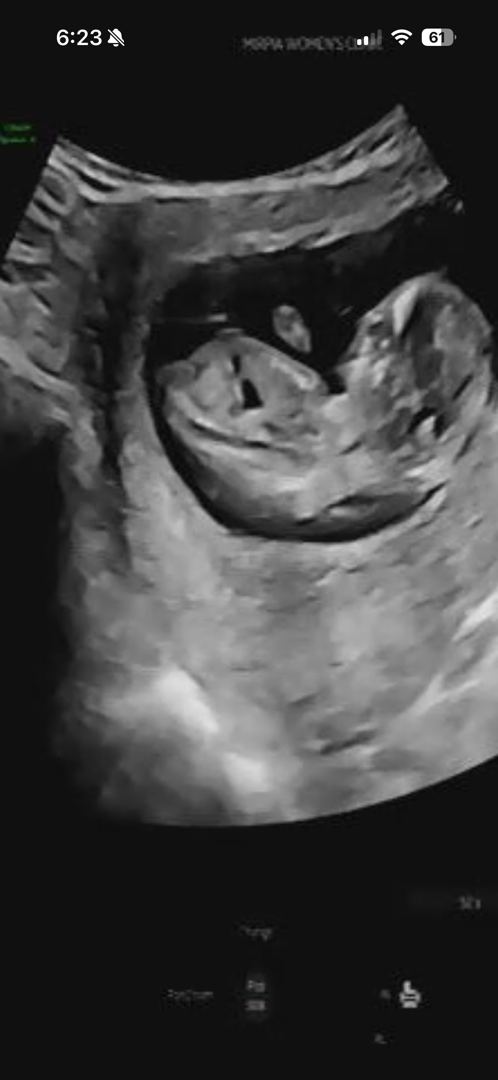

12주 2일차 각도법 성별

둘째인데 성별이 너무 궁금해요~🙂 알 수 있을ㄲㅏ요?